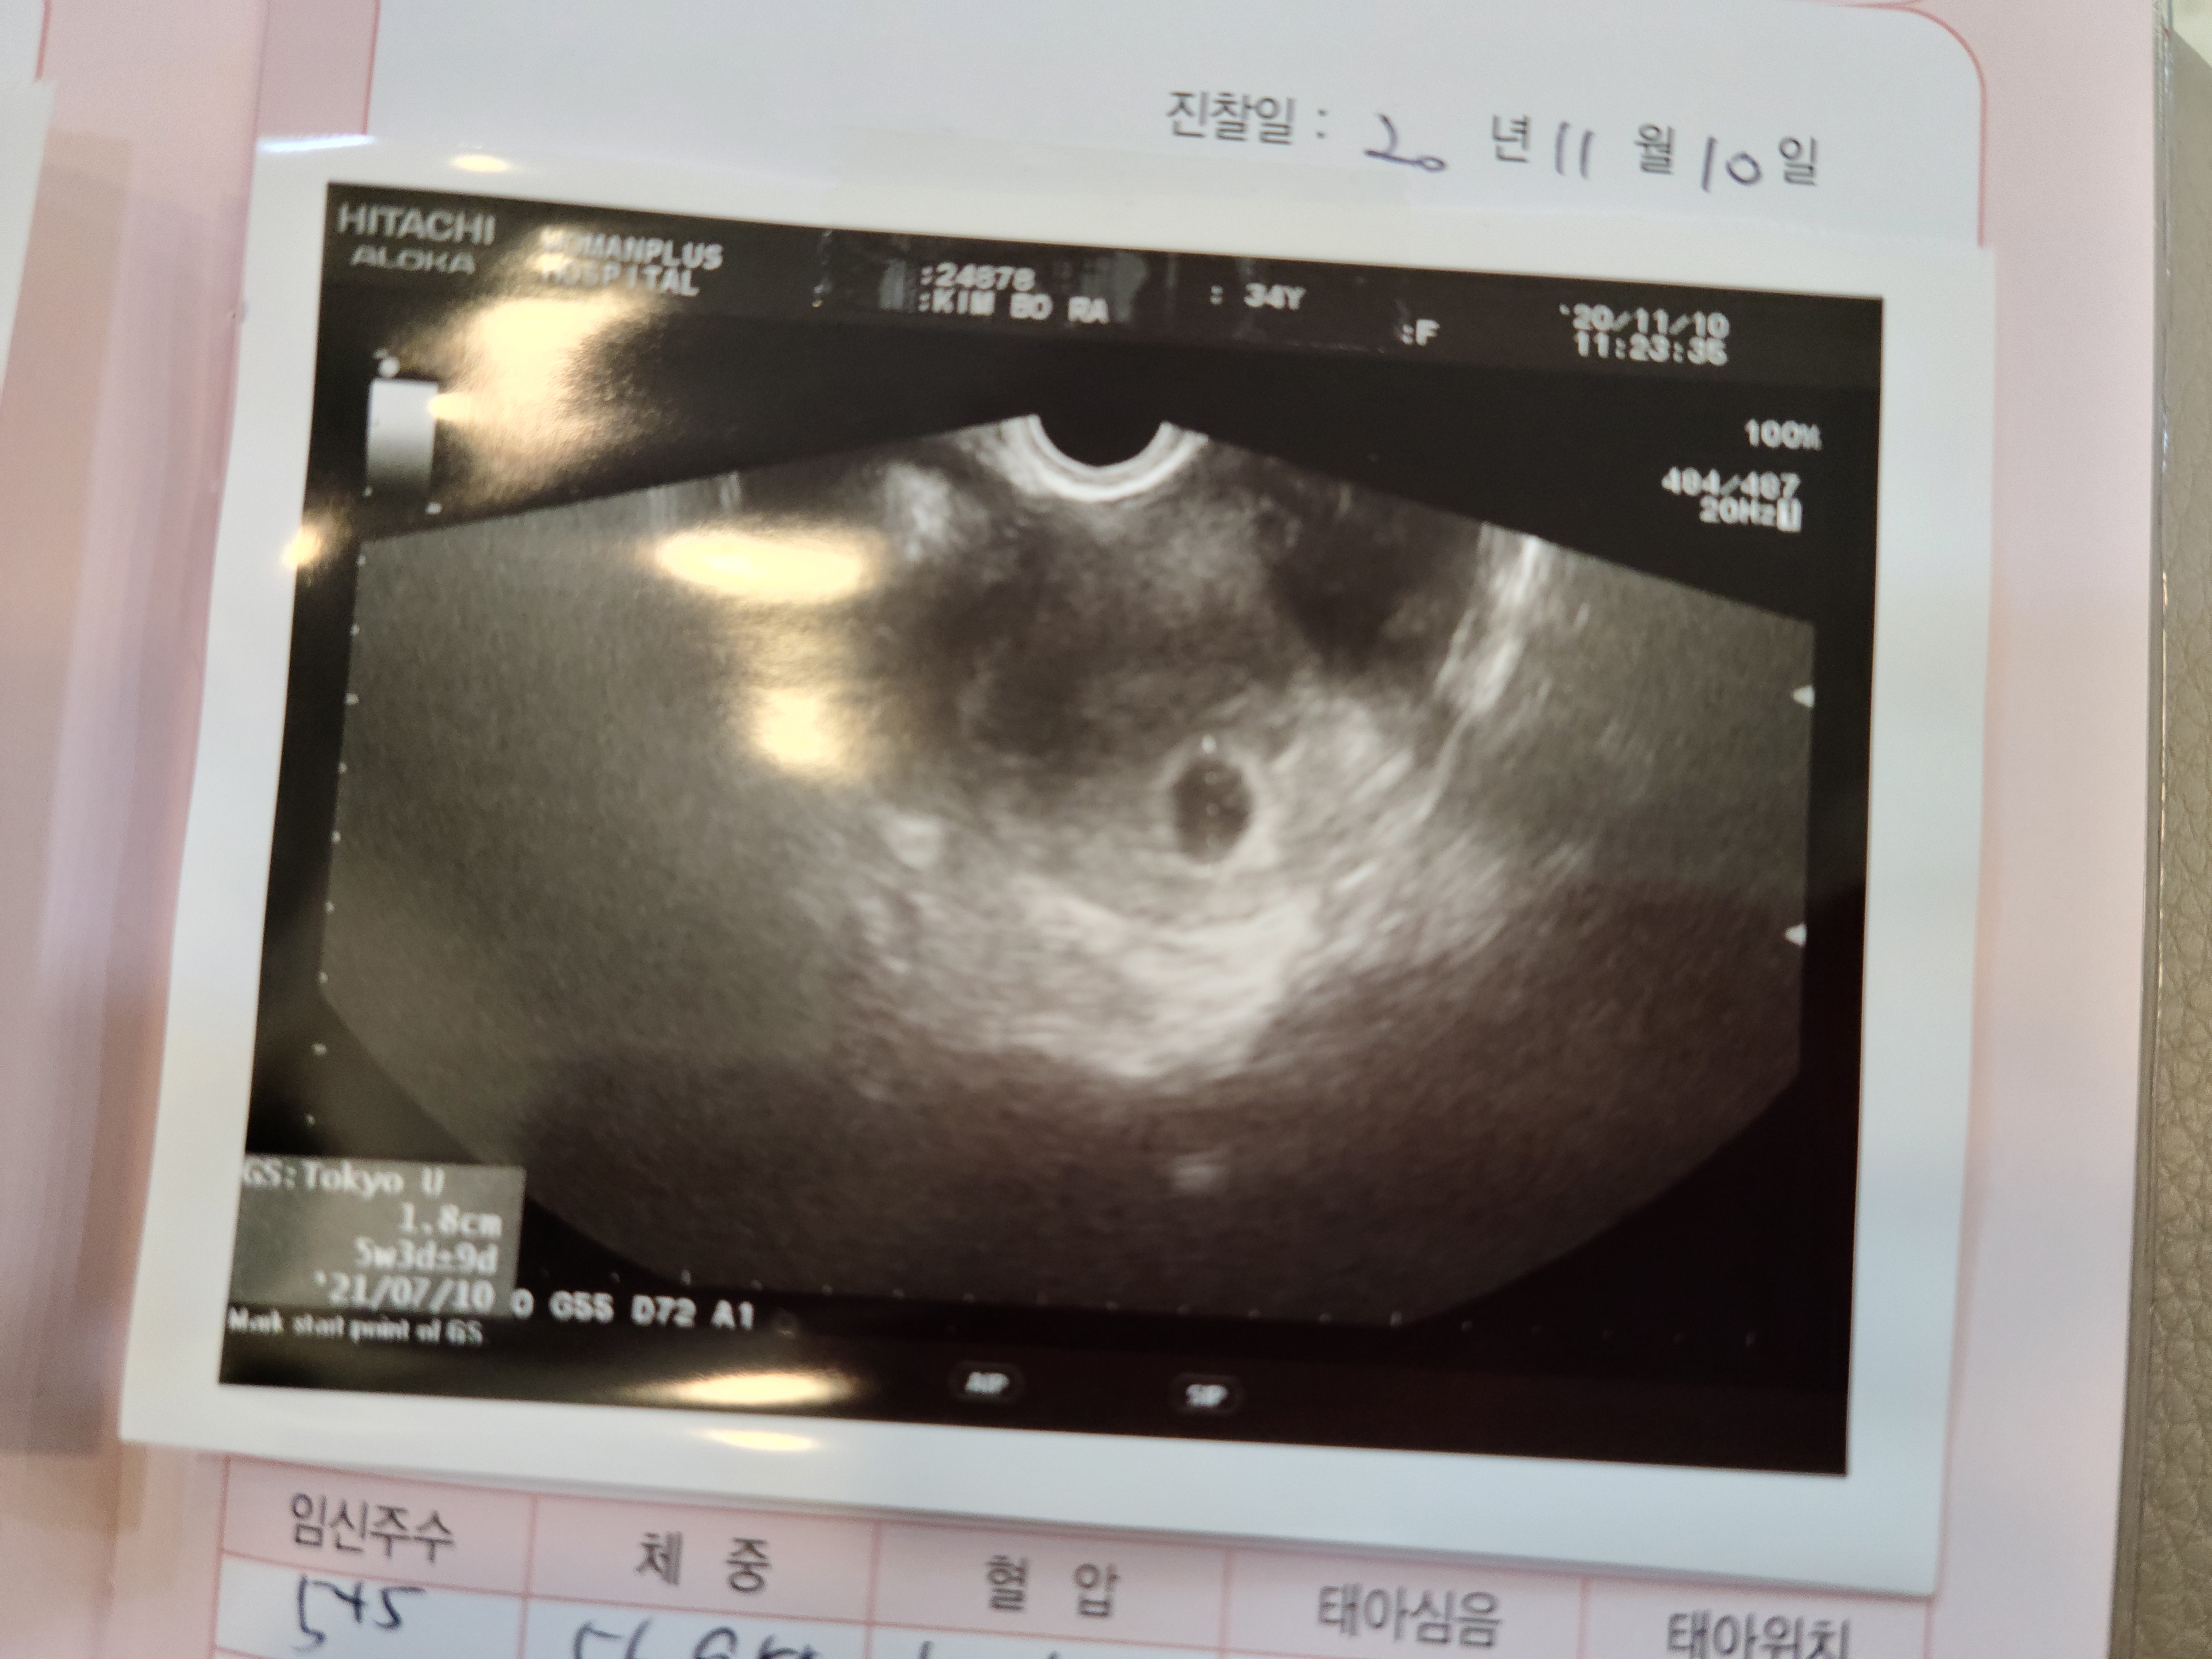

두번째, 이제 니가 처음 보이기 시작했어